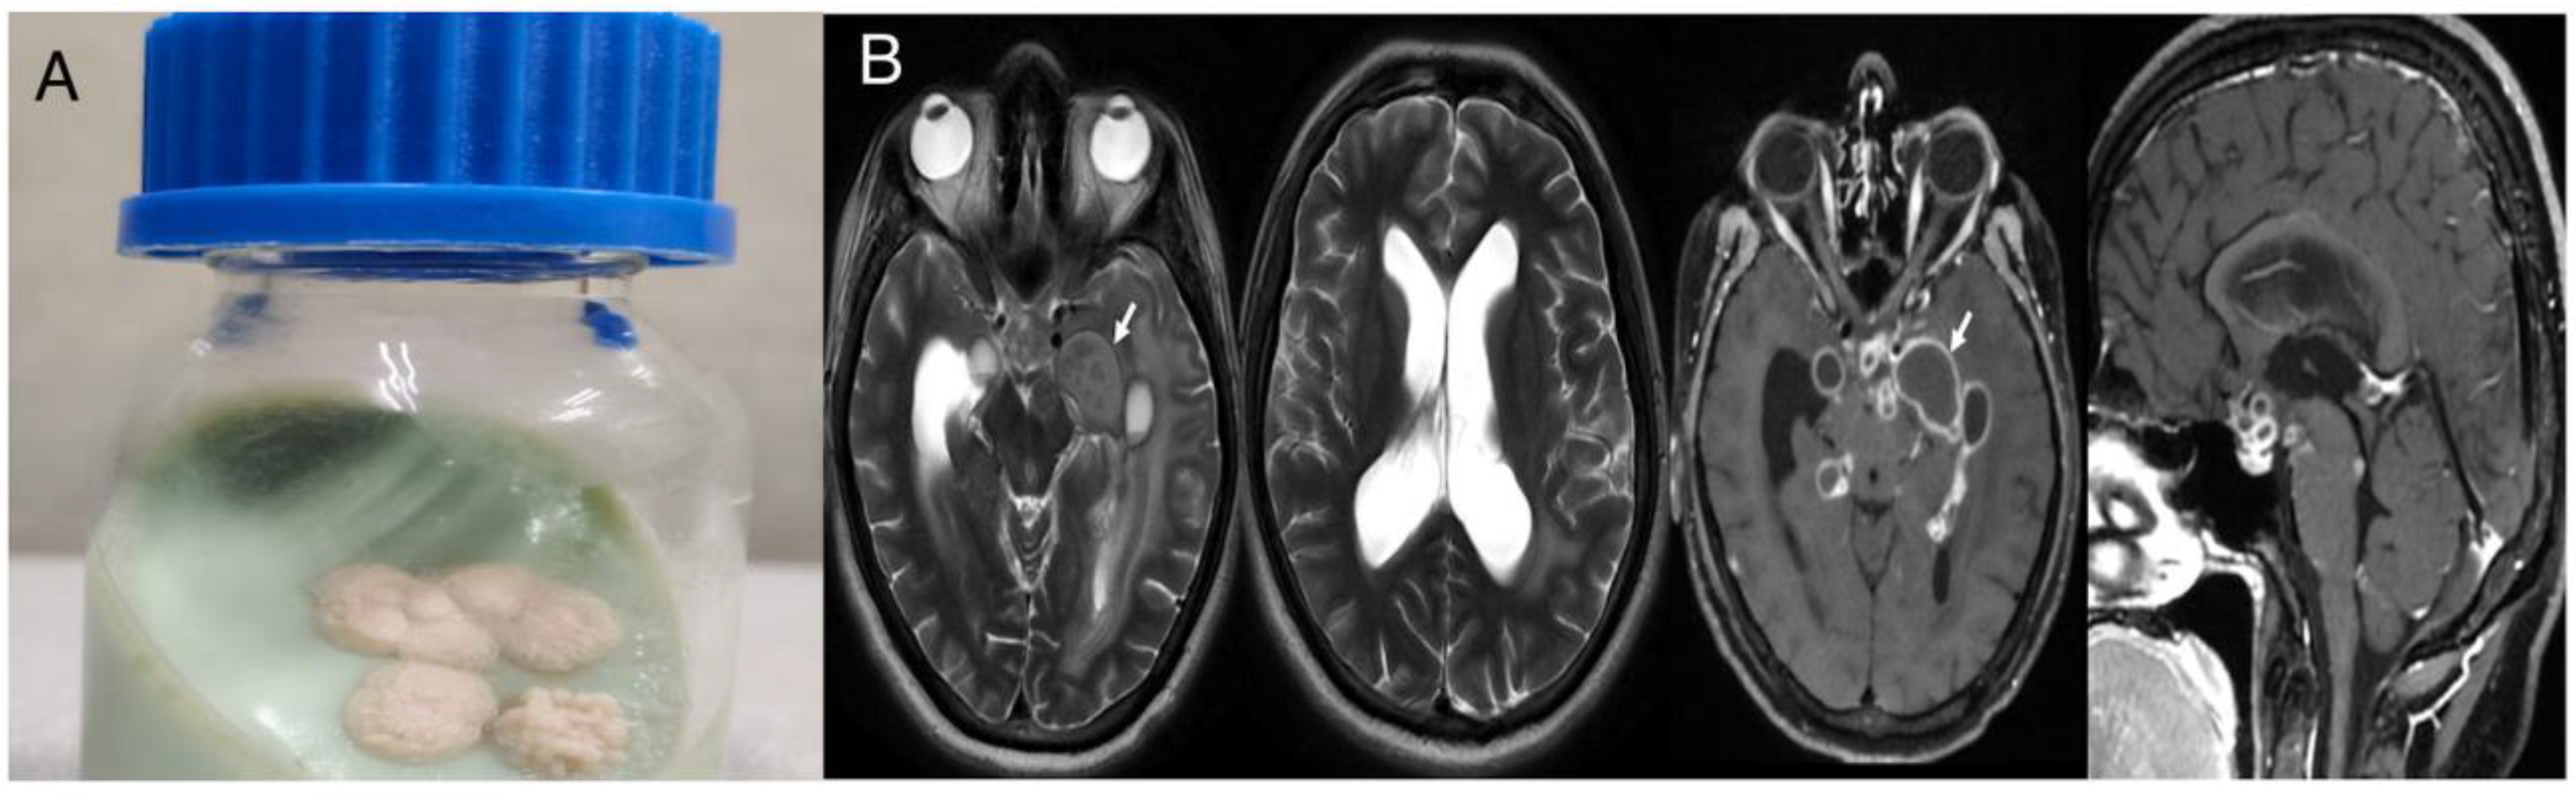

Case 2